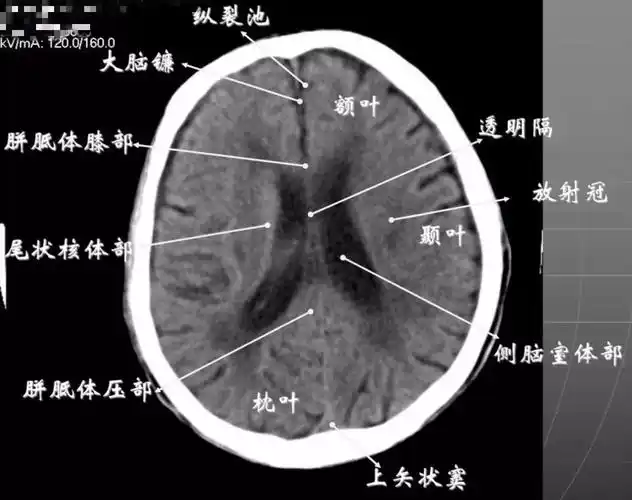

ct提示左侧基底节,丘脑,颞叶,枕叶广泛性脑出血.

读懂头颅ct并不难教你成为读片小能手

头颅ct解剖ppt

基 线 上 40mm 第三脑 室前部层面: 重点观察内囊, 基底节和丘脑